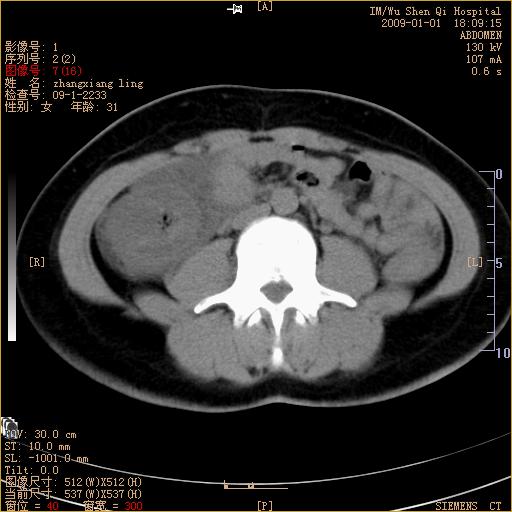

标题: CT17527:F31Y,腹痛伴血便9小时 [打印本页]

标题: CT17527:F31Y,腹痛伴血便9小时

升结肠肠壁不规则增厚,肠腔狭窄,考虑升结肠占位,建议增强扫描

升结肠肠壁不规则增厚,肠腔狭窄,考虑升结肠占位,建议增强扫描,不除外肠套叠.

升结肠肠壁不规则增厚,似呈同心圆改变,其有积液。结合病史首先考虑肠套叠伴肠壁坏死可能性大,结肠肿瘤待排。

升结肠肠壁不规则增厚,似呈同心圆改变,其有积液。结合病史首先考虑肠套叠伴肠壁坏死可能性大,结肠肿瘤待排。支持!(发病急,无过去史,应首先考虑:肠套叠)

患者已手术,结果肠系膜血栓形成肠坏死

患者已手术,结果肠系膜血栓形成肠坏死。

结合病史并看到升结肠增粗及局限的腹腔积液,考虑肠套叠伴肠壁坏死可能性大

结果:患者已手术,结果肠系膜血栓形成肠坏死。回过头再看局部肠壁增厚有分层(高密度坏死及低密度水肿)表现。